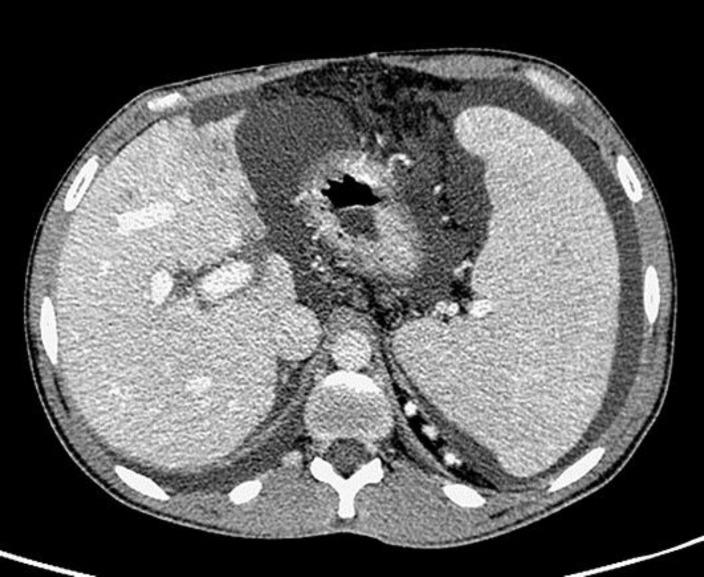

A 37-year-old male, who at the age of 8 years had been treated for right-sided Wilms' tumor with nephrectomy, radiotherapy, and chemotherapy, presented with noncirrhotic portal hypertension (NCPH), grade 2 esophageal varices, and ascites. A CT scan demonstrated hypoplasia of liver segments 2 and 3. A liver biopsy showed portal tract fibrosis without cirrhosis, with histological features of NCPH. Liver vein catheterization showed a normal portal pressure gradient of 5 mm Hg while spleen to hepatic vein pressure was 29 mm Hg. NCPH after therapy for Wilms' tumor is described in children within the first few years after treatment. This is the first case report in which the patient first presented symptoms as an adult, many years after cancer treatment.

摘要

一名37岁男性,8岁时因右侧肾母细胞瘤接受了肾切除术、放疗和化疗,现出现非肝硬化性门静脉高压(NCPH)、2级食管静脉曲张和腹水。CT扫描显示肝段2和3发育不全。肝活检显示门静脉纤维化但无肝硬化,具有NCPH的组织学特征。肝静脉插管显示门静脉压力梯度正常为5 mmHg,而脾静脉至肝静脉压力为29 mmHg。肾母细胞瘤治疗后的NCPH在治疗后的头几年内在儿童中有所描述。这是首例患者在癌症治疗多年后成年才首次出现症状的病例报告。